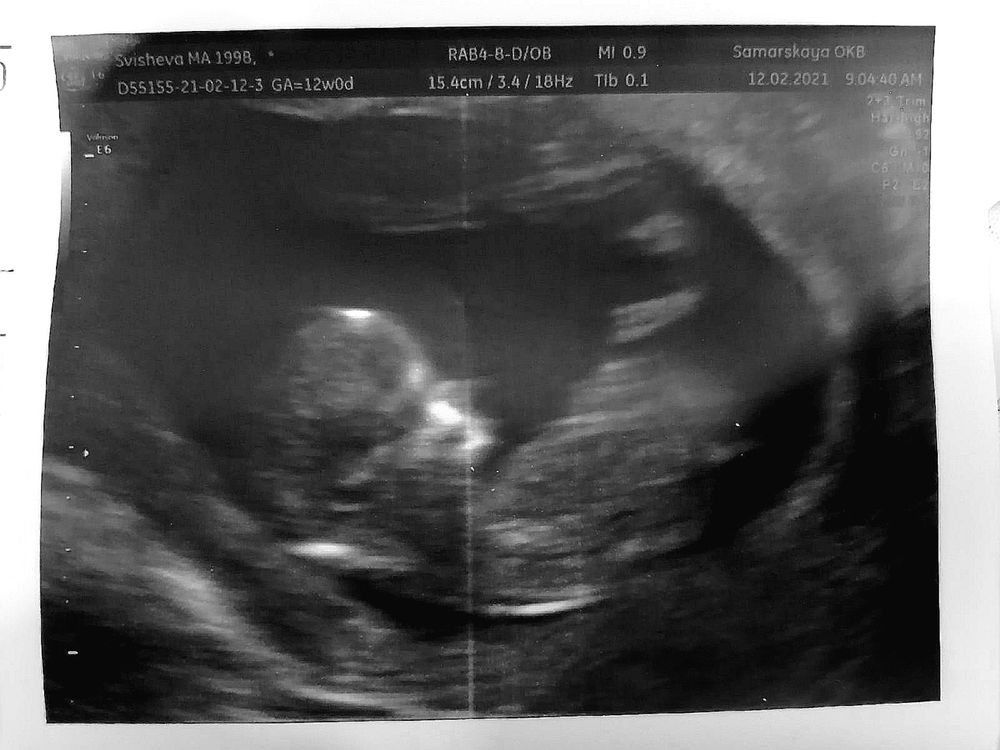

Думала, что натощак не смогу доехать до больницы, примерно час в пути. Утром стошнило, конечно, от голода, но поездка далась легче, чем ожидала. Узи заняло порядка 10 минут, делали только по животу, в конце показали детёныша, сказали, что всё хорошо, и опять нахлынули эмоции. Уже совсем совсем человек, активный малый, помахал ручкой, потоптал ножками. Про пол не спрашивала, не хочу слышать предположения, лучше позже, но точно. Результаты прикрепляю, и фотографию, за которую 500р запросили. Ну а как же без фотографии, надо же папочке показать, а то из-за карантина не пускают сопровождающих.